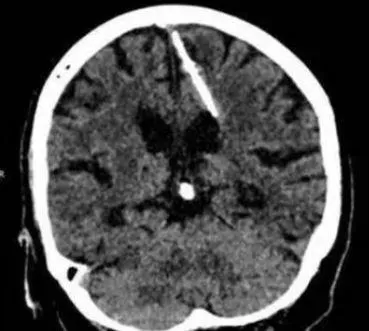

腦部

針

CTWANT